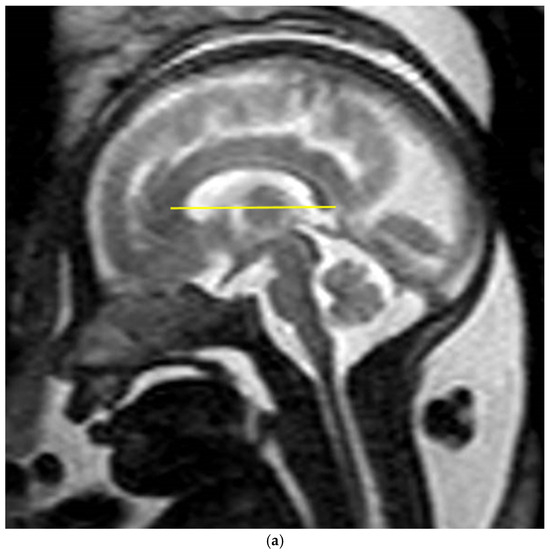

Mid-sagittal sections were used to assess and measure the biometry of the CC. Measurements were conducted in accordance with reference charts for fetal cerebral MRI biometry [15], using a straight rostrocaudal line from the most anterior aspect of the genu to the most posterior end of the splenium, parallel to the axial axis of the head (Figure 1a,b) [33,34]. Among the multiple MRI images available for each fetus, the image chosen for the measurement was based on the best mid-sagittal section, in which the brainstem and cerebellum were visible [33].

Figure 1.

Mid-sagittal slice of the fetal brain in (a) T2-weighted image and (b) DTI with an example of fetal CC biometry measurement demonstrated by the yellow line. The images were taken from two different fetuses.